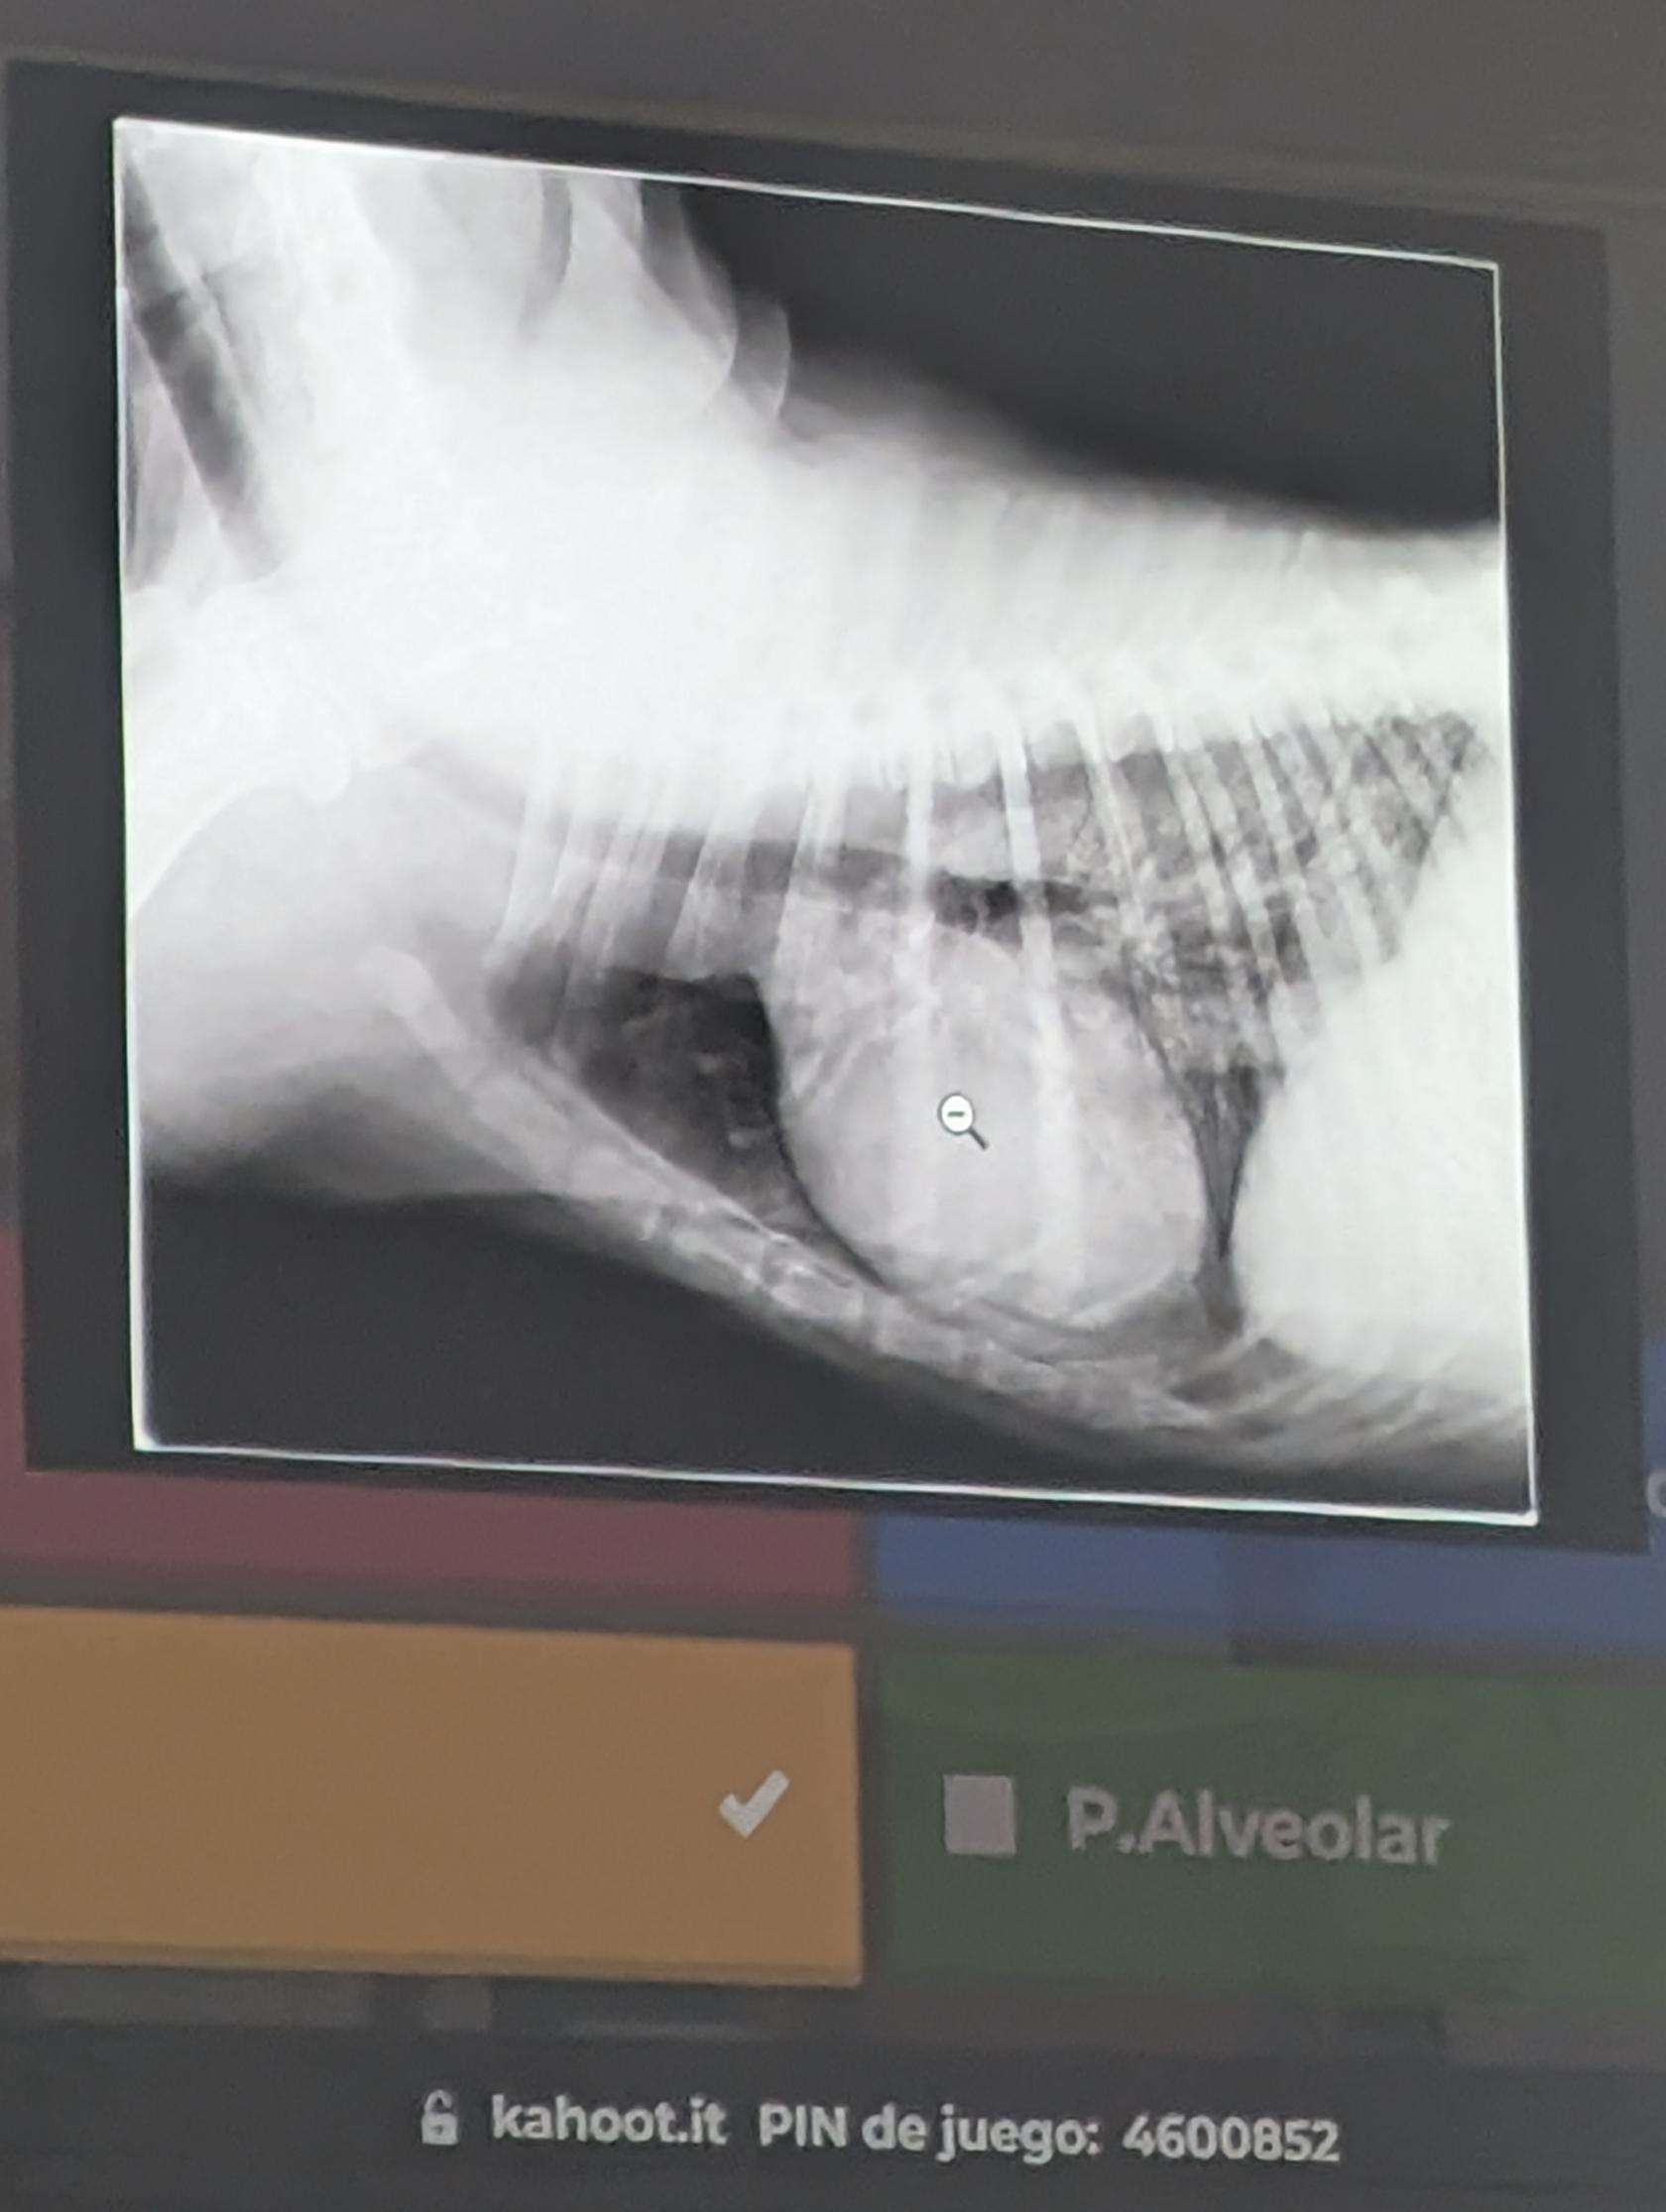

1) Una respuesta correcta

- Patron Intersticial (Difusa, no estructurado, se ve la vena cava y aun hay negros, por eso no es alveolar) IMPORTANTE Patrones bronquiales no suelen entrar porque se ven mal de los donuts